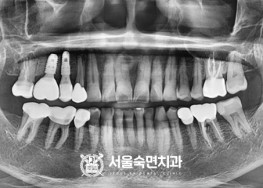

임플란트-치료-전후사진

서울대학교-출신-보건복지부-인증-통합치의학과-전문의-2인-책임관리